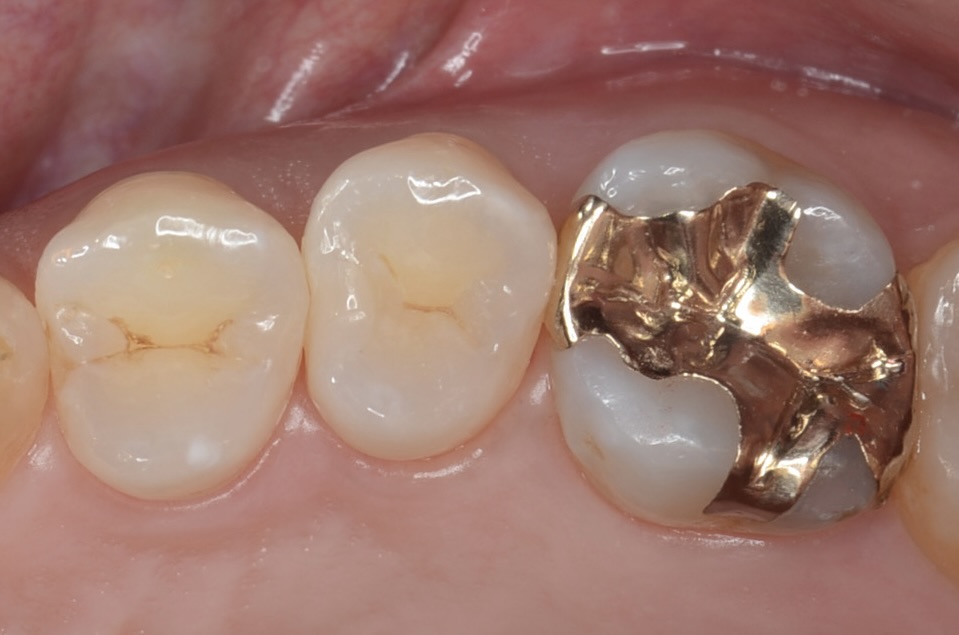

神経を取りたくない・MTAセメント・歯髄保存療法虫歯の治療・ダイレクトボンディング

30代 虫歯治療 VPT(歯髄温存療法)ダイレクトボンディング #35

Before

After

| 年齢 | 40代 | 治療方法 | VPT(歯髄温存療法)/ダイレクトボンディング |

|---|---|---|---|

| 性別 | 女性 | 通院回数 | 2回 |

| 主訴 | むし歯を治したい /神経を取りたくない | 費用 | 175,000円(税込) |

| 治療のメリット | 神経を保存できる・歯を削る量を少なくできる・自然な見た目・境目がピッタリできる | ||

| 治療のデメリット | 虫歯の大きさ・神経の状態によっては神経を保存できない場合がある | ||